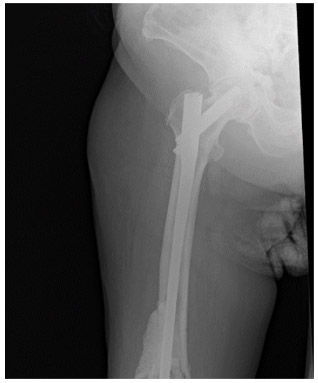

Post-surgery: The X-ray shows the application of bone cement and nails to the site of the removed metastatic focus.